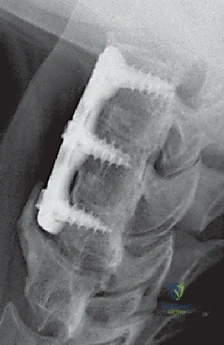

الخطوة 7: التثبيت المعدني (Instrumentation)

لضمان الاستقرار الفوري ومنع حركة الطعم العظمي حتى يكتمل الالتحام (والذي يستغرق أشهراً)، يقوم الدكتور هطيف بتثبيت شريحة معدنية صغيرة من التيتانيوم على الجزء الأمامي من الفقرتين باستخدام براغي دقيقة.

بعد إزالة القرص، تتبقى فجوة بين الفقرتين. لمنع انهيار هذه المسافة ولتحفيز التحام الفقرتين معاً، يتم إدخال "طعم عظمي" أو قفص صناعي (Cage) مصنوع من مادة PEEK أو التيتانيوم ومملوء بمادة عظمية.

الخطوة 6: زراعة الطعم العظمي (Bone Graft Insertion)